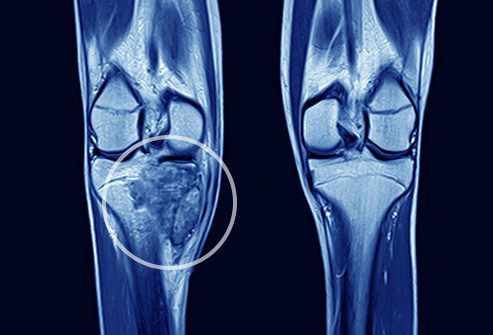

3- امآرآی (MRI – تصویربرداری تشدید مغناطیسی)

- امآرآی به جای استفاده از اشعه ایکس، با استفاده از میدانهای مغناطیسی تصاویر دقیقی از بدن تولید میکند. اندازهی تومور را میتوان با امآرآی اندازهگیری کرد. به کمک امآرآی، انکولوژیستهای ارتوپدی میتوانند بهترین روش جراحی برای بیماران سرطانی را برنامهریزی کنند.